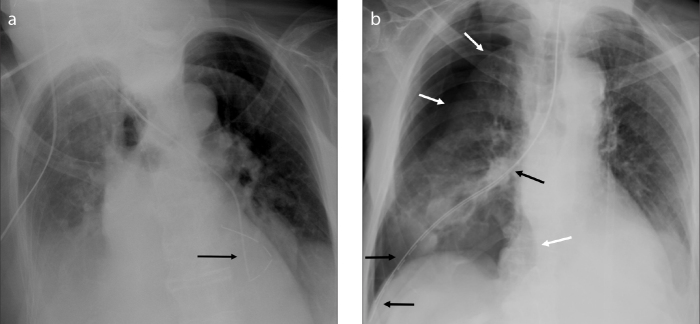

Figure 1.

A technically correct bedside chest X-ray performed in the intensive care unit. The exam allows to evaluate the position of inserted chest devices (chest tubes, black asterisks; endotracheal tube, white asterisk; pulmonary artery catheter, black arrowhead; nasogastric tube – proximal portion, white arrowhead) and to detect the presence of bilateral pleural effusions (white arrows) and the occurrence of soft tissue emphysema (black arrow). The patient underwent heart surgery and prosthetic valves, median sternotomy wires and external cardiac monitor wires are also present.